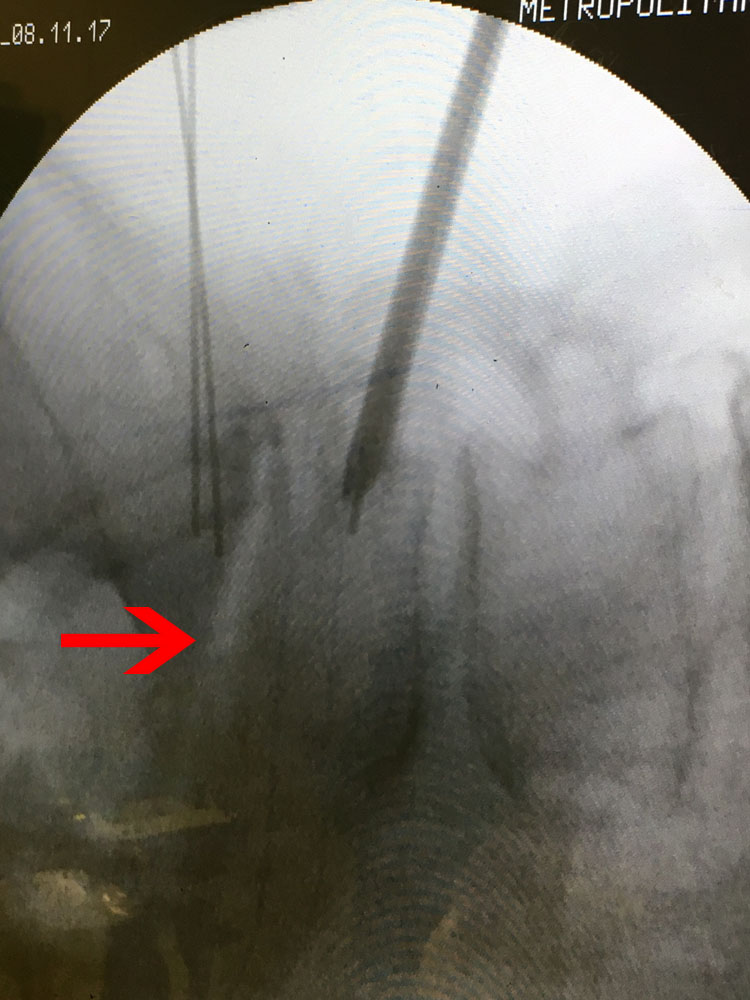

Εικ 3 – (α,β,γ,δ,ε,,στ,ζ,η,θ) Δια-επεμβατικές φωτογραφίες βιοψίας με χρήση του συστήματος πλοηγήσεως O-ARM. Οστικά δείγματα έχουν ληφθεί από το μεσοσπονδύλιο δίσκο Ο5-Ι1 και τους εκατέρωθεν σπονδύλους Ο5 και Ι1.

(ι,ια) Δείγματα οστικά και κυτταρικά.

Τα αποτελέσματα της ιστολογικής και κυτταρολογικής εξέτασης δεν έδωσαν απόλυτα σαφή διάγνωση για το υφιστάμενο παθολογικό υπόστρωμα, ωστόσο οι κυριότερες ενδείξεις ήταν υπέρ φλεγμονής σταφυλοκοκκικής αιτιολογίας.